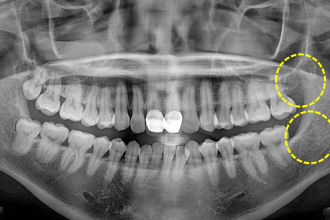

사랑니발치

굿프렌즈 치과 임상 케이스